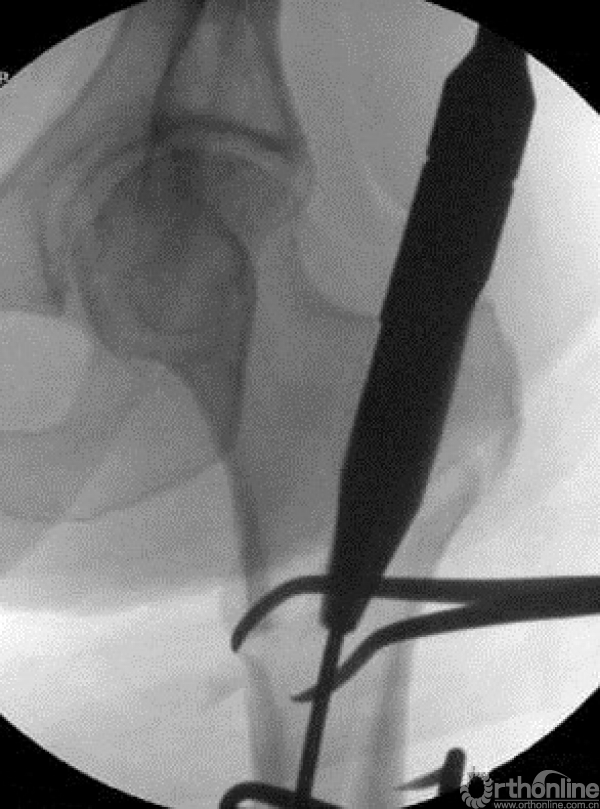

同时可以对于近端复位不良时,可以采用顶棒纠正前后旋转,克氏针纠正内外旋转。

或采用钳加复位,复位之后可以较好的植入头钉。